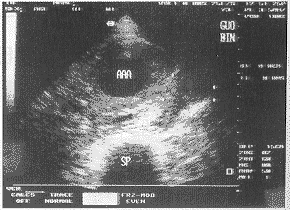

中国超声医学杂志991038 患者男,72岁。1998年2月,患者无意中发现脐部左上方有一包块。超声检查显示:髂总动脉分叉前腹主动脉呈梭形扩张,长度110mm,最大内径70mm。瘤壁呈不规则增厚,最大厚度(后壁)18mm,横切面显示后壁有半弧形无回声区(15mm×8mm)。超声诊断:腹主动脉瘤并夹层瘤。1999年2月10日,患者感到腰部持续性钝痛,向臀部放散。2月11日因疼痛加剧而入院。查体:体温37℃,血红蛋白:97g/L,脐部左上方可触及20cm×15cm搏动性包块。入院第二天,体温37.8℃,血红蛋白:89g/L,超声所见:腹主动脉瘤大小较一年前无明显变化,但瘤壁有明显增厚,尤其是后壁增厚至36mm,后壁内原有的夹层瘤已由无回声变成低回声,考虑有机化,可显示夹层瘤的破裂口(图1),横切面显示瘤体外周左侧有低回声区,提示腹膜后血肿形成(图2)。肝段腹主动脉,髂总动脉内径正常,双侧股动脉内显示大范围斑块。第三天,体温38.2℃,血红蛋白76g/L。入院第四天,又出现腰部剧痛,仍有发热,体温38℃,血红蛋白降至70g/L,超声所见:腹主动脉瘤后壁除原有的夹层瘤外,在其浅层可见新出现的液性无回声区(40mm×25mm×7mm),有破裂口与腹主动脉瘤相通,并显示有血流信号,超声诊断:腹主动脉瘤并夹层瘤再形成。第五天上午,再次复查超声:腹主动脉瘤体外周左侧低回声区有明显扩大,提示血肿增大(图3)。血红蛋白已减少至54g/L,体温38℃。当晚患者突感腰部绞痛,难以忍受,伴有全身大汗,20分钟后意识突然丧失,腹部膨隆,继而心跳、呼吸停止,经抢救无效,死亡。临床诊断:腹主动脉瘤并夹层瘤破裂。

动脉瘤周边的腹膜后血肿(↓)范围尚小

图2 腹主动脉横切面